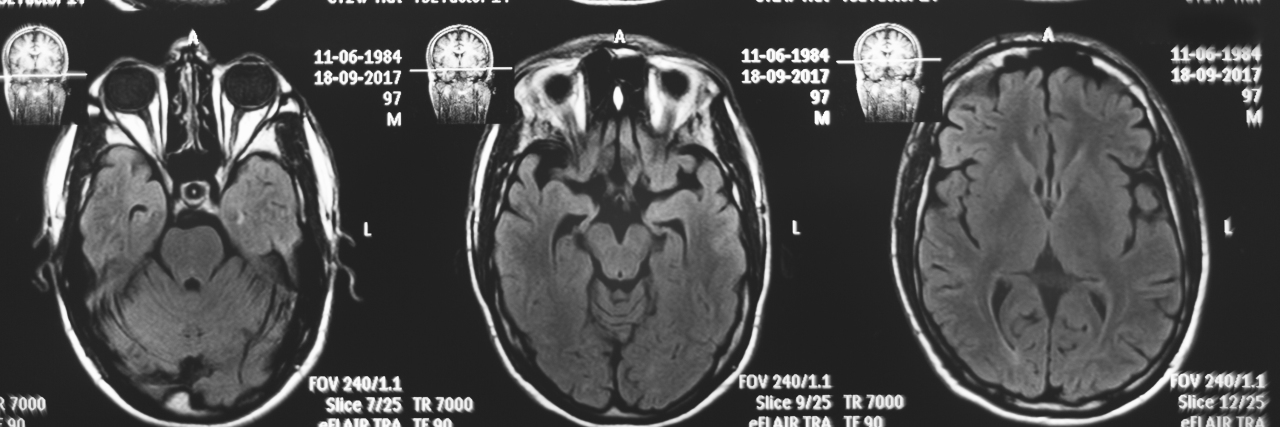

I gained a new career path; examining my own CT scans intrigued me. I chose to pursue a Bachelor’s degree in Radiologic Technology.